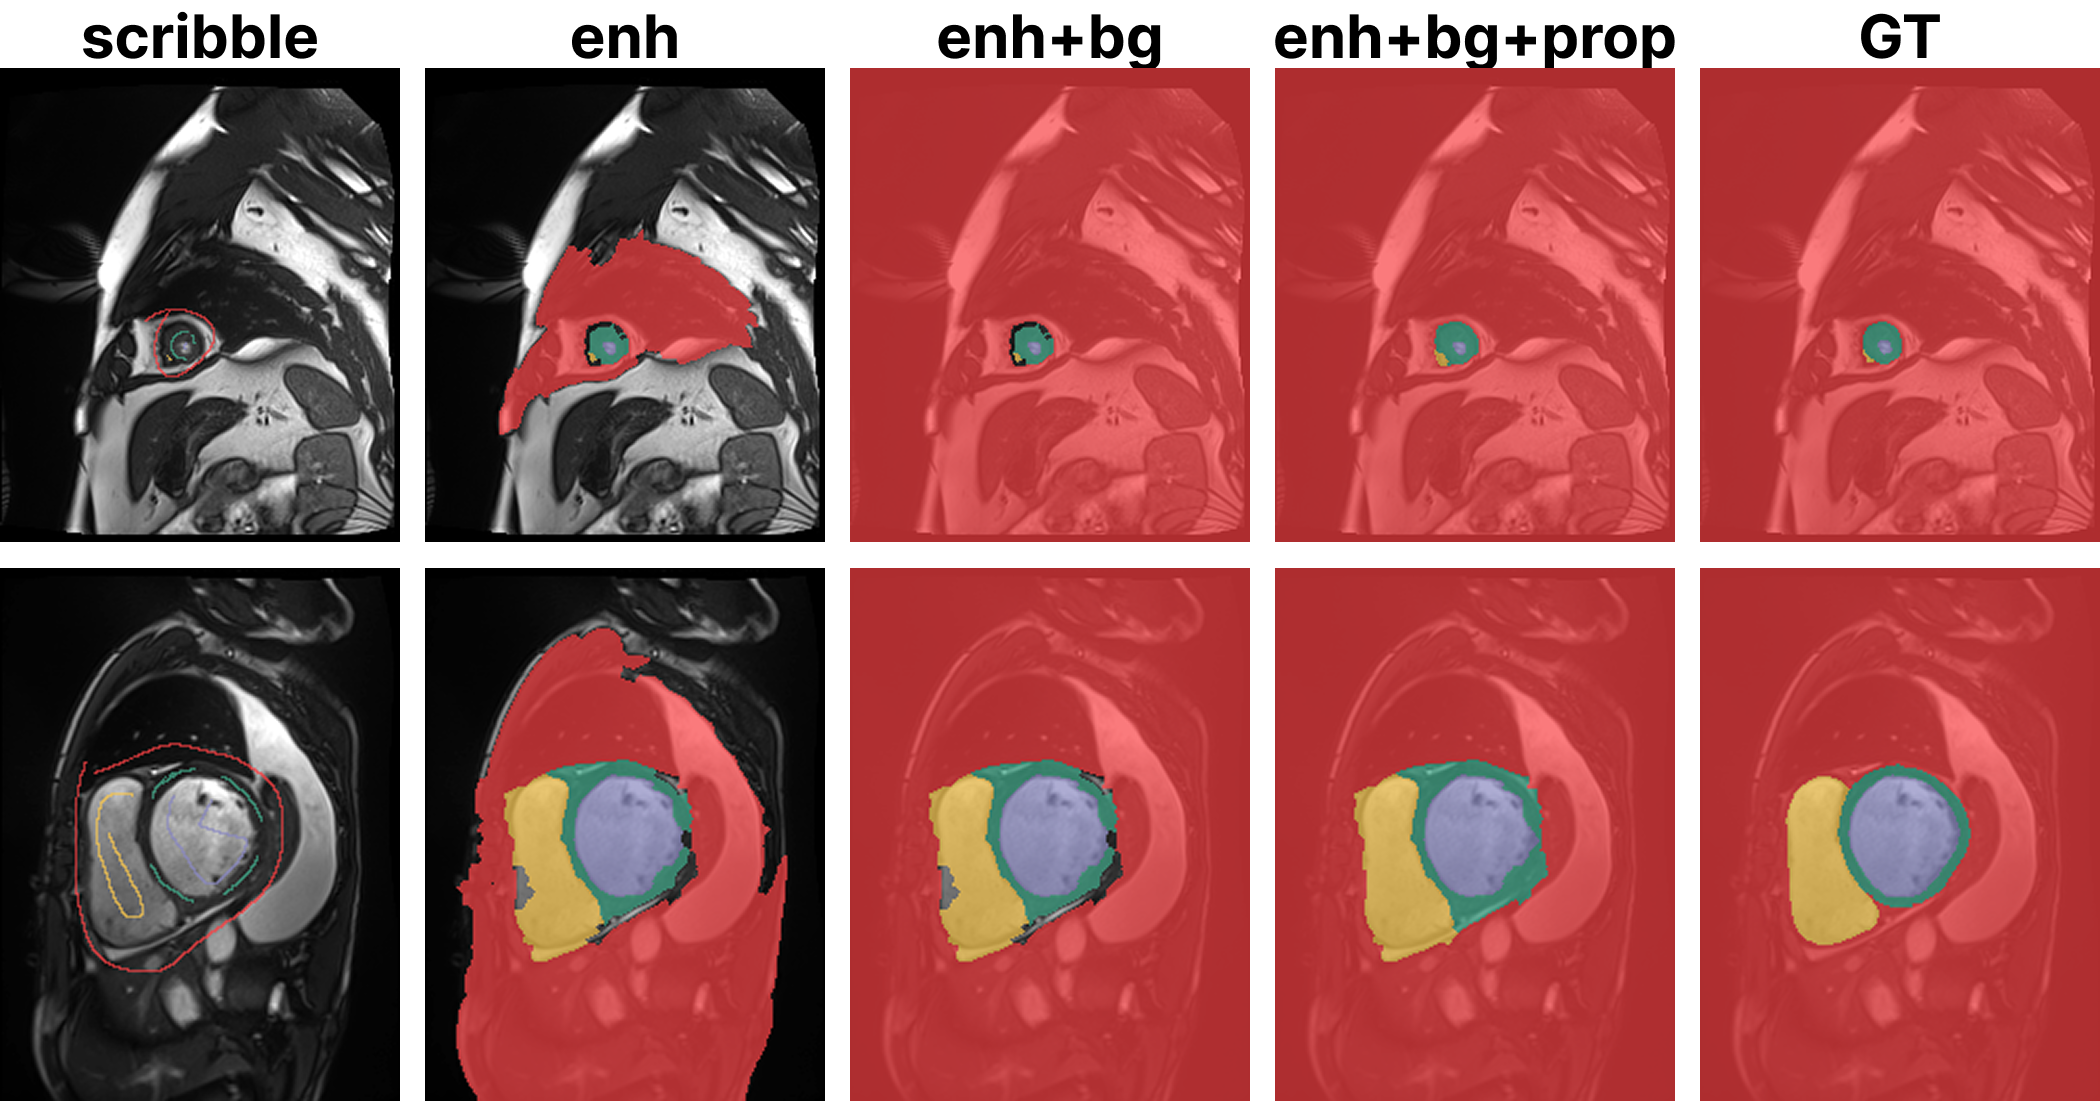

Refer to caption

Fig. 3: Qualitative comparison among enhancement results with different PLESS setups on a sample from ACDC.

To identify the most effective PLESS configuration, an ablation study is conducted on two key components. Different strategies for scribble spreading are first analyzed, considering three progressive variants. The baseline scribble spreading (enh) corresponds to the original waterfall-based region expansion proposed in [4] and enh+bg is the introduced background expansion variant. Finally, full region propagation (enh+bg+prop) is applied, where the remaining unlabeled pixels are iteratively assigned labels from neighboring regions until full image coverage is achieved. The three different stages of PLESS are visualized in Fig. 3.

The second key component is the tolerance level. Table 4 reports the performance of the ScribbleVS network under different PLESS configurations and tolerance levels, ranging from 25% to 100%. The enh+bg variant achieves the best performance across two of the measures (DSC and ASD). Performance is strongest at 25% and 75%, while a degradation is observed at 100%. This suggests that aggressive scribble spreading at full tolerance can introduce noise, as the enhanced annotations may contain inaccuracies and ambiguities. At later training stages, pseudo-labels generated by the teacher and student networks can be more reliable than the propagated enhancements themselves. This leads to better performance when scribble spreading is not applied in the later episodes. In most cases, the variant without full propagation (enh+bg) outperforms enh+bg+prop, indicating that complete label propagation introduces incorrect labels in uncertain regions, which degrades performance.